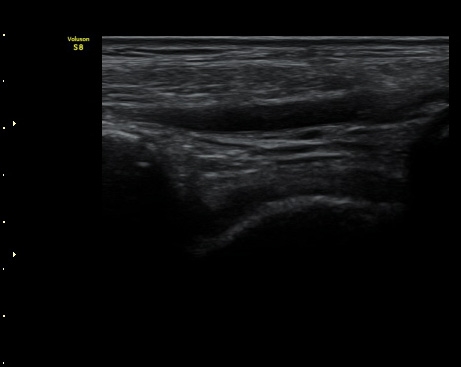

Àü¹æ°Å°ñºñ°ñÀδë Á¾´Ü¸é°Ë»ç¿¡¼­ ¹Ì¼¼ÇÑ ºñ°ñ¿¡¼­ ¹Ú¸®µÈ ¹Ì¼¼ °ñÆí°ú

ÀδëÀÇ Àú¿¡ÄÚ ºÎÁ¾ÀÌ °üÂûµÈ(±×¸² 2).